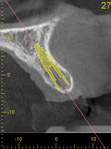

Fig 12. Virtual planning of a posterior implant (Fig 12) resulted in inadequate restorative running room for the crown emergence profile in the cross-sectional CBCT image. Revision (Fig 13) resulted in deeper positioning of the implant for restorative running room but necessitated transcrestal sinus elevation, possibly with the addition of bone via the osteotomy to tent the membrane.

Figure 12

Fig 13. Virtual planning of a posterior implant (Fig 12) resulted in inadequate restorative running room for the crown emergence profile in the cross-sectional CBCT image. Revision (Fig 13) resulted in deeper positioning of the implant for restorative running room but necessitated transcrestal sinus elevation, possibly with the addition of bone via the osteotomy to tent the membrane.

Figure 13